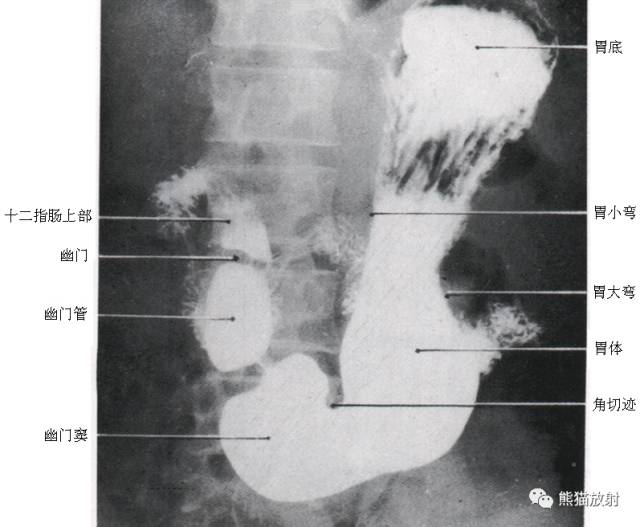

5 Stomach 胃

1 Fundus 底,2 Abdominal esophagus 腹段食管,3 Cardia 贲门,4 Lesser curvature 小弯,5 Duodenum 十二指肠,6 duodenal bulb 十二指肠球部,7 Gastric folds (posterior wall) 胃皱襞(后壁),8 Pylorus 幽门,9 Body of the stomach 胃体,10 Angular notch 角切迹,11 Greater curvature 大弯,12 Pyloric antrum 幽门管,12 + 13 Antrum 胃窦

6 Stomach and Duodenum 胃和十二指肠

1 duodenal bulb 十二指肠球部,2 Pylorus 幽门,3 Pyloric antrum 幽门管(窦),4 Descending duodenum 十二指肠降段,5 Papilla of Vater 十二指肠乳头